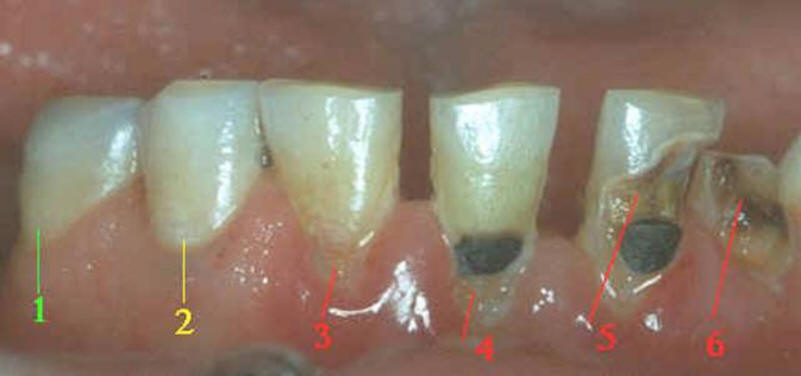

ASPECTO VISUAL: Cuando se ve húmeda no hay evidencia de

cambio en el color atribuibles a la actividad de caries, pero después

del secado con aire por 5 segundos, una opacidad de caries o cambio de

color (mancha blanca o lesión marrón) es visible, lo cual no es consistente con

la apariencia clínica del esmalte sano, el cambio de color se

limita al fondo de la fosa o fisura.

La desmineralización progresa,

aumentando el tamaño y el número de poros en la sub-superficie.

La capa superficial del esmalte se

encuentra intacta con poca pérdida mineral. No hay

invasión bactriana en la sub-superficie ni tampoco se ha

formado una cavidad. La mancha blanca es observada

en esmalte húmedo.

ASPECTO VISUAL:

Al observar el

diente en estado húmedo verá una decoloración (mancha blanca

/ marrón)

en el fondo de la fosa y fisura, que desborda hacia las

paredes. (mas ancha que la fosa y fisura) las manchas

no tienen brillo y es consistente con desmineralización.

Lesión

incipiente en progreso (activa):

-

La superficie del

esmalte es blanquecina / amarillenta.

Es opaca con pérdida

de brillo; se siente áspero cuando se mueve

la punta de la sonda suavemente a través de

la superficie.

La lesión está en un

área de estancamiento de placa madura, es

decir: en fosas y fisuras, cerca del margen

gingival y superficie proximal, por debajo

del punto contacto.

Si esta cerca del la

encía, esta suele sangrar.